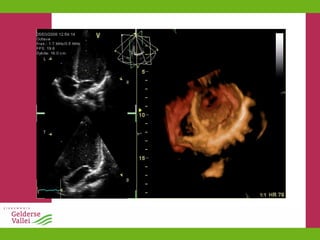

New Kids on

the Block Slokdarmecho Contrast-verrijkt Weefsel (Tissue Doppler) 3D